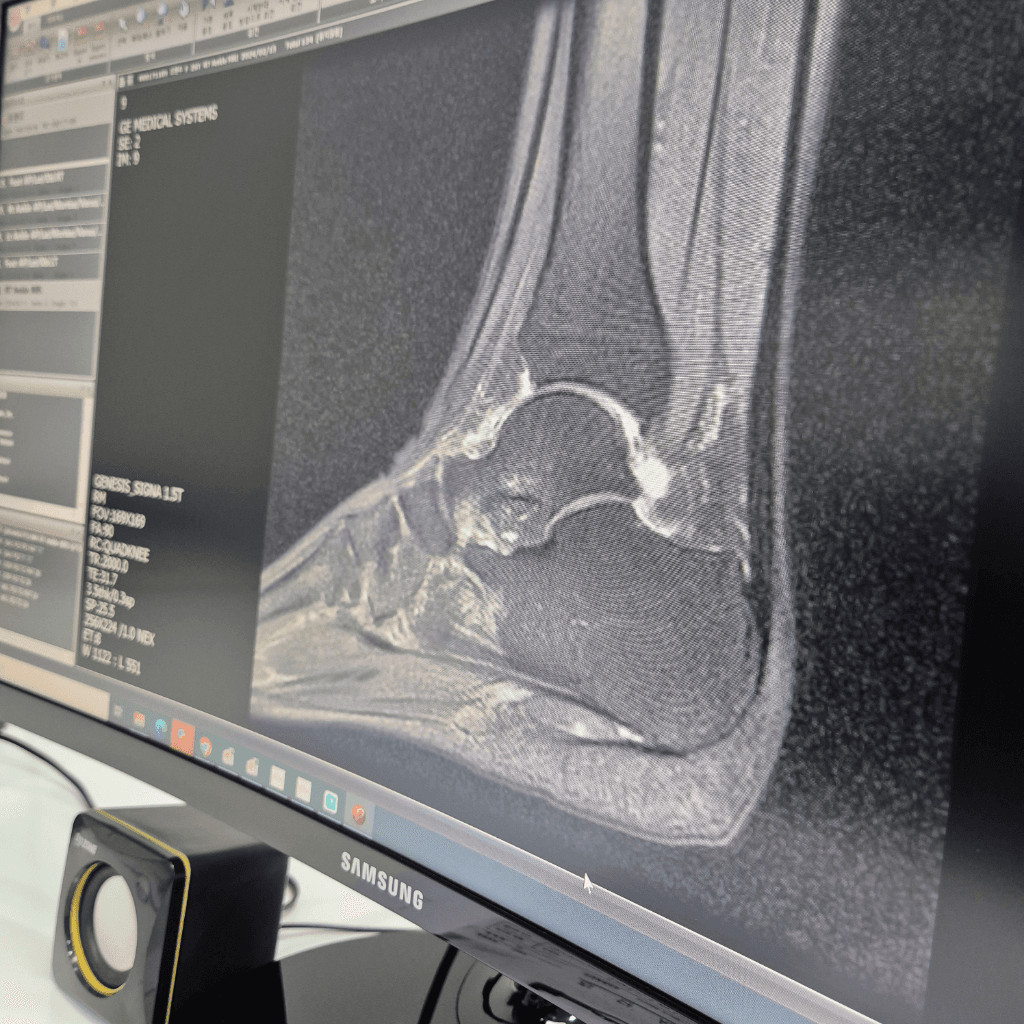

같은 mri자료로 의사선생님 소견이 다른데 다른 분들이 보시기엔 어떤가요?

A 선생님 께서는 발목거골골절로 진단을 내려주셨고

B 선생님 께서는 종골의골절로 진단을 내려 주셨는데

A병원이 mri를 찍은 병원이고 B병원이 집근처라 지금도 다니고 A선생님 소견을 전해드리니 복숭아뼈 아래는 아무말 없냐고 물으셨고 저도 여쭤본 질문이기에 없었다는 답을 드렸습니다.

사진이 흐릿하긴 하나 어떤거 같은가요?? 두분의 말씀이 다 맞나요?

mri만으로는 화질이나 각도에 따라 거골 골절과 종골 골절이 혼동될 수 있으며 두 선생님 의견 모두 일부 타당할 수 있습니다. 보험 진단서 발급은 실제 골절 위치에 따라 주수 장해 판정이 달라질 수 있으므로 정확한 구분이 필요합니다. ct는 뼈 골절 경과와 회복 상태를 가장 잘 확인할 수 있는 검사라 아직 통증과 부종이 남아 있다면 촬영이 도움이 됩니다!